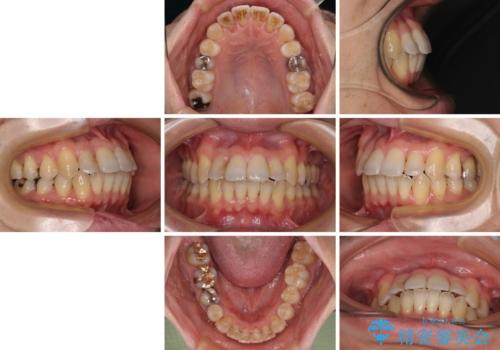

前歯のクロスバイト 目立たないワイヤー装置で矯正治療

舌の突出癖の影響か、下顎前歯がなかなか整わず、治療期間は予定よりも長期間となりました。

舌突出癖改善のトレーニングの重要性を認識することとなりました。